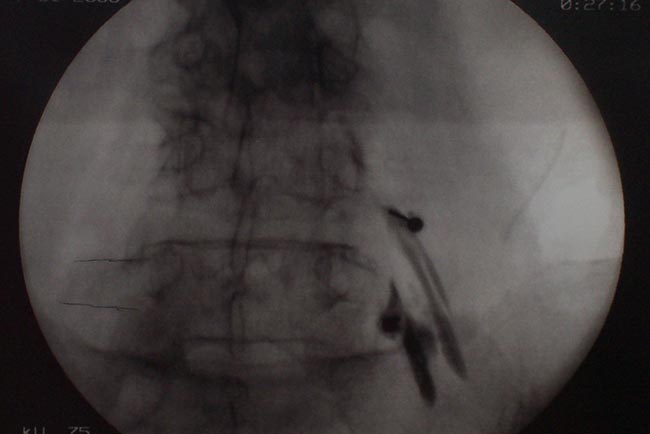

Nas radiografias de frente e de lado do sacro podemos observar a agulha e o contraste preenchendo o espaço sacral e iniciando seu deslocamento até as raízes lombares. Em geral a ponta da agulha deve estar localizada próximo a vértebra S2.